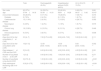

Sample characteristics.

| Total | Discharged(46; 40.4%) | Hospitalisation without AV(53; 46.5%) | AV in ICU(15; 13.2%) | P | |

|---|---|---|---|---|---|

| Sex: male | 65 (57%) | 24 (52.2%) | 32 (60.4%) | 9 (60.0%) | 0.691 |

| Age | 57.44±14.18 | 53.39±14.31 | 58.91±14.29 | 64.67±9.42 | 0.015* |

| Concomitant diseases | 30 (26.3%) | 8 (17.4%) | 15 (28.3%) | 7 (46.7%) | 0.074 |

| Diabetes | 9 (7.9%) | 2 (4.3%) | 6 (11.3%) | 1 (6.7%) | 0.431 |

| Cardiovascular disease | 13 (11.4%) | 2 (4.3%) | 7 (13.2%) | 4 (26.7%) | 0.052 |

| Neurological disease | 3 (2.6%) | 1 (2.2%) | 1 (1.9%) | 1 (6.7%) | 0.575 |

| Chronic lung disease | 18 (15.8%) | 6 (13.0%) | 8 (15.1%) | 4 (26.7%) | 0.446 |

| Immunosuppressive treatment | 6 (5.3%) | 3 (6.5%) | 3 (5.7%) | 0 (0.0%) | 0.608 |

| Days from SO to first consultation (1st CXR) | 5.5 [4−7] | 7.00 [3.75−8.25] | 6.00 [4.00−7.00] | 5.00 [3.00−5.00] | 0.111 ** |

| Days from SO to first consultation (2nd CXR) | 10 [8−13] | 12.50 [9.00−16.00] | 10.00 [8.00−12.00] | 9.00 [6.00−10.00] | 0.002 ** |

| Days between 1st CXR and 2nd CXR | 5 [3−6.5] | 6.00 [4.00−8.50] | 4.00 [3.00−6.00] | 4.00 [3.00−6.00] | 0.001 ** |

| Number of lung fields in the 1st AI-CXR | 1 [0−2] | 0.00 [0.00−2.00] | 1.00 [0.00−2.50] | 2.00 [0.00−3.00] | 0.271 ** |

| Number of lung fields in the 2nd AI-CXR | 3 [0.75−5] | 1.00 [0.00−3.00] | 4.00 [2.00−6.00] | 6.00 [5.00−6.00] | <0.001 ** |

| Daily radiological worsening rate in AI-CXR | 0.33 [0−0.75] | 0.00 [0.00−0.33] | 0.50 [0.00−1.00] | 1.00 [0.33−1.00] | <0.001 ** |

The results are shown as a function of absolute frequency (percentage), mean±standard deviation in the case of normal distribution, and median (25th and 75th quartiles) in case of non-normal distribution. Assisted ventilation means the need for non-invasive ventilation or endotracheal intubation. χ2 tests, *ANOVA test, **Kruskal-Wallis test.

Assisted ventilation and admission to the intensive care unit were not a direct consequence of the patient's second clinical evaluation, but of the final result after a period of hospitalisation.

Abbreviations: ICU: intensive care unit; SO: symptom onset; AV: assisted ventilation.

The number of lung fields affected in AI-CXR was greater in patients who required assisted ventilation, but statistical significance was only reached in AI-CXR2 (6.00 IQR: 5.00−6.00; 4.00 IQR: 2.00−6.00 and 1.00 IQR: 0.00−3.00 with respect to the need for assisted ventilation, hospital admission and discharge, respectively; p<0.001). The timing of CXR2 from the onset of symptoms ranged between eight and 13 days (IQR), with greater variability in milder patients discharged again, with an IQR of nine to 16 days (Table 1). The median time between CXR1 and CXR2 was five days (IQR: 3.0–6.5), but this fell to four (IQR: 3.00−6.00) in patients who required hospital admission or assisted ventilation (p= 0.001).

Progression of affected lung fields between AI-CXR1 and AI-CXR2 was an independent risk factor for the need for assisted ventilation. In fact, the daily radiological worsening rate of AI-CXR was higher in patients who required assisted ventilation, with values of 1.00 (IQR: 0.33−1.00); 0.50 (IQR: 0.00−1.00) and 0.00 (IQR: 0.00−0.33) for the need for assisted ventilation, hospital admission and discharge, respectively (p<0.001; Table 1). The AUC of the daily radiological worsening rate in AI-CXR to predict the need for assisted ventilation was 0.771 (95% CI: 0.683−0.845; p< 0.001; Table 2). When pneumonia progressed ≥0.5 lung fields per day, there was a 4.2-fold increase in the need for assisted ventilation according to binary logistic regression (95% CI: 1.19–14.52; p= 0.025, Table 3) with sensitivity of 66.67 (95% CI: 38.4−88.2), specificity of 74.75 (95% CI: 65.0−82.9), PPR of 2.64 (95% CI: 1.6−4.3), NPR of 0.45 (95% CI: 0.2−0.9), PPV of 28.6 (95% CI: 14.6−46.3) and NPV of 93.7 (95% CI: 85.8−97.9) for the need for assisted ventilation (Table 2). When pneumonia progressed by 0.67 lung fields per day, the specificity reached 80.81 (95% CI: 71.7−88.0) and the NPV 94.1 (95% CI: 86.8−98.1), with the sensitivity figure remaining at 66.67 (38.4−88.2) (Table 2).

Diagnostic performance of the number of lung fields in the first and second AI-CXR and daily radiological worsening rate in AI-CXR.

| AUC | Threshold | Sensitivity | Specificity | PPR | NPR | PPV | NPV | |

|---|---|---|---|---|---|---|---|---|

| Number of lung fields in the 1st AI-CXR | 0.590 (0.494−0.681) | >0 | 73.33 (44.9−92.2) | 45.45 (35.4−55.8) | 1.34 (0.9−1.9) | 0.59 (0.2−1.4) | 16.7 (8.6−27.9) | 91.8 (80.4−97.7) |

| Number of lung fields in the 2nd AI-CXR | 0.810 (0.726−0.878) | >4 | 80.00 (51.9−95.7) | 73.74 (63.9−82.1) | 3.05 (2.0−4.6) | 0.27 (0.10−0.8) | 31.6 (17.5−48.7) | 96.1 (88.9−99.2) |

| Daily radiological worsening rate in AI-CXR | 0.771 (0.683−0.845) | >0.5 | 66.67 (38.4−88.2) | 74.75 (65.0−82.9) | 2.64 (1.6−4.3) | 0.45 (0.2−0.9) | 28.6 (14.6−46.3) | 93.7 (85.8−97.9) |

| >0.6667 | 66.67 (38.4−88.2) | 80.81 (71.7−88.0) | 3.47 (2.0−6.0) | 0.41 (0.2−0.8) | 34.5 (17.9−54.3) | 94.1 (86.8−98.1) |

The data in brackets are confidence intervals of 95%.

AI-CXR: CXR processed with the AI tool; AUC: area under the curve; NPR: negative probability ratios; NPV: negative predictive value; PPR: positive probability ratios; PPV: positive predictive value.

Binary logistic regression models for the rate of radiological worsening of the CXR processed with the AI tool ≥0.5 lung fields (model 1) and number of affected lung fields in the second CXR processed with the AI tool (model 2).

| Variable | [0.2−5] Model 1 (N=114, CCR=86.8%) | [0.6−9] Model 2 (N=114, CCR=86.8%) | ||||||

|---|---|---|---|---|---|---|---|---|

| OR | LL 95% CI | UL 95% CI | p-value | OR | LL 95% CI | UL 95% CI | p-value | |

| Age | 1.028 | 0.978 | 1.081 | 0.275 | 1.037 | 0.979 | 1.097 | 0.213 |

| Sex: male | 1.014 | 0.314 | 3.270 | 0.982 | 1.005 | 0.289 | 3.489 | 0.994 |

| Any concomitant illness: yes | 1.536 | 0.417 | 5.650 | 0.519 | 1.654 | 0.415 | 6.600 | 0.476 |

| Constant | 0.017 | n/a | n/a | 0.030 | 0.001 | n/a | n/a | 0.001 |

| DRWR-AI-CXR ≥0.5 lung fields | 4.158 | 1.191 | 14.518 | 0.025 | n/a | n/a | n/a | n/a |

| LF-AI-CXR2 | n/a | n/a | n/a | n/a | 2.046 | 1.298 | 3.227 | 0.002 |

The reference categories for dichotomous qualitative variables were “sex: female,” “any concomitant disease: no”.

95% CI: 95% confidence interval; AI-CXR: CXR processed with the AI tool; CCR: correct classification rate; DRWR-AI-CXR: daily radiological worsening rate of the CXR processed with the AI tool; LF-AI-CXR2: number of lung fields in the second AI-CXR; LL: lower limit; n/a: not applicable; OR: odds ratio; UL: upper limit.

Although the LF-AI-CXR2 achieved a better AUC (0.810; 95% CI: 0.657−0.886; Table 2), no significant differences were obtained between LF-AI-CXR2 and the daily radiological worsening rate of AI-CXR in the pairwise comparison of the ROC curves (p= 0.550), and the prognostic capacity of the need for assisted ventilation of LF-AI-CXR2 was worse according to the binary logistic regression analysis, with a relative risk of 2.05 (95% CI: 1.30–3.23; p= 0.002, Table 3).